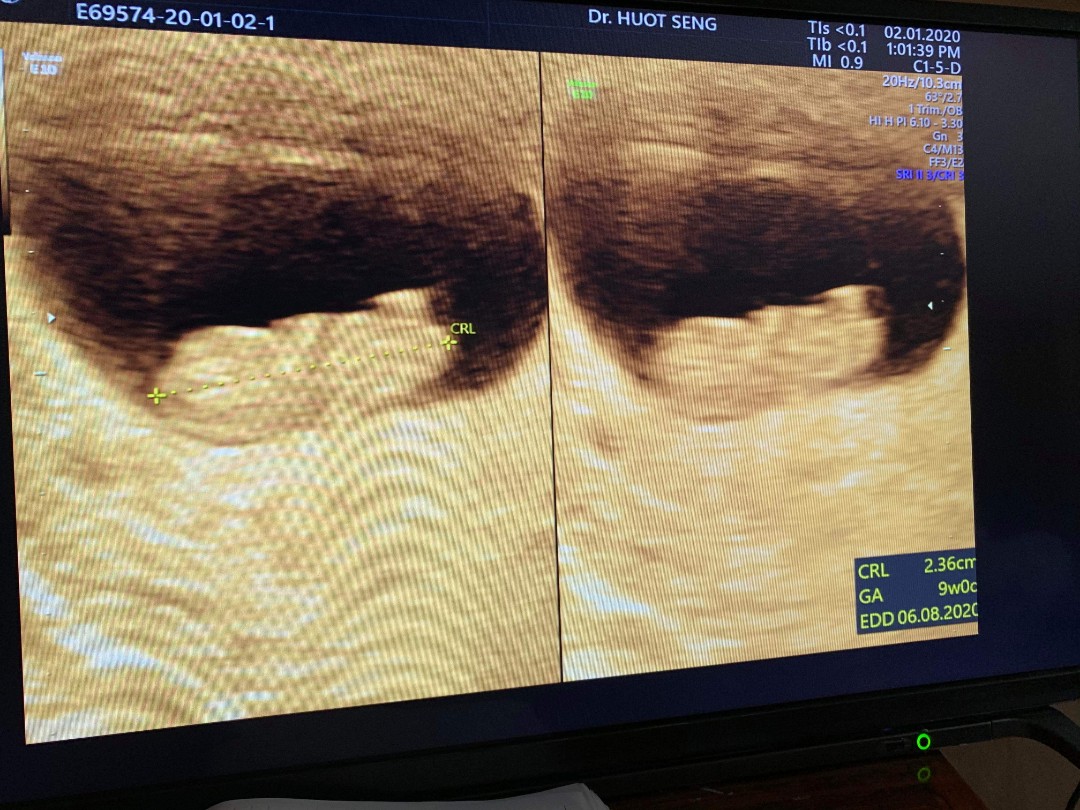

ยู้ ฮู 9 วีคคคค